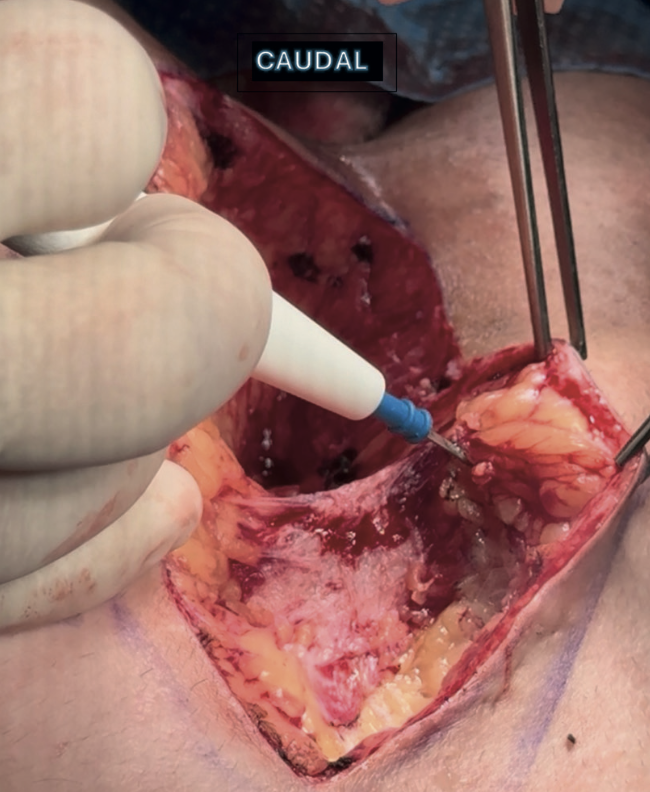

Imágenes y Cirugía

Beatriz Remezal Serrano, Mónica Patricia Rey Riveiro, Pilar Serrano Paz